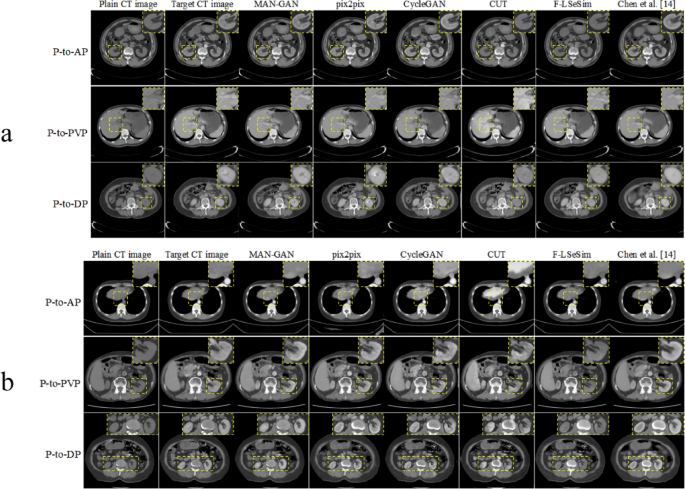

To prove the effectiveness of our proposed method, we compare the proposed MAN-GAN with the existing methods on the main test dataset. As shown in Table 1, our method obtained the best PSNR and SSIM in all generations of the three phases in comparison to the current methods. Figure 2a shows the enhanced CTs generated from the main dataset for different phases of CT translation. In P-to-AP translation, as shown in the magnified patches, MAN-GAN can synthesize CT images with more discriminative features than can other methods. When translating from plain to PVP CT images, the synthetic CT image generated by MAN-GAN is contrast-enhanced more accurately than that generated by other methods, suggesting the superiority of the proposed MAN-GAN to existing methods. As shown in Table 2, the mask images for P-to-AP translation preserve the best performance, with a PSNR of 25.2738, in comparison with the mask images for other phrases. In Fig. 3, we qualitatively evaluate the generated mask images for CT translation by computing the PSNR and SSIM between the real and fake mask images. The distributions of the PSNR and SSIM for different phases are relatively concentrated.

Visual comparison of existing methods and MAN-GAN on Dataset 1 (a) and Dataset 3 (b).

To verify the generalization ability of the proposed MAN-GAN, we tested our method on dataset 3 for external validation. As listed in Table 4, we compared MAN-GAN with existing methods for three-phase translation. Figure 2b shows enhanced CT images generated by MAN-GAN and existing methods for three-phase translation. In P-to-DP translation, MAN-GAN can enhance kidney regions more precisely than other methods, as shown in the magnified patches, suggesting its superiority to existing methods.